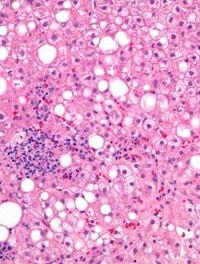

La prise en charge médicamenteuse de la stéatohépatite non alcoolique (NASH) est encore en attente d’une molécule douée de propriétés [...]

Le traitement de la NASH est au cœur d’un enjeu scientifique, médical et industriel sans précédent. Cette affection, corrélée au surpoids [...]

La stéatohépatite non alcoolique (NASH) fait l’objet de nombreuses recherches avec 196 molécules dans le pipeline des traitements en [...]

Le foie gras non alcoolique (FGNA) demeure une affection métabolique dont sa forme la plus grave appelée NASH (stéato-hépatite non [...]

L’hépatite stéatosique non alcoolique est devenue la première des pathologies hépatiques chroniques et l’une des principales causes [...]

La stéato-hépatite non alcoolique (SHNA) est une affection fréquente caractérisée histologiquement par l’association d’une stéatose, [...]